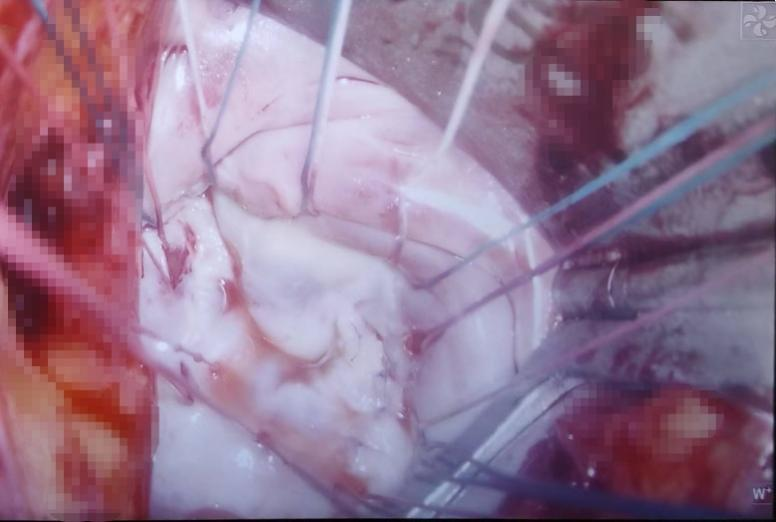

手术当日,贾一新借助胸腔镜放大的视野,通过仅6cm的微创切口,精准定位,面对增厚挛缩的瓣膜,小心谨慎地用刀片一点点剔除钙化斑块,避免一旦失误,导致不得不放弃修复选择置换。每一刀修剪,贾一新都小心比对术前超声模型,确保修复后的瓣叶开闭自如。随后,他用坚韧的成型线固定人工瓣环,使其恢复完整形态,最后通过反复高压注水试验,以保证修复后的瓣膜能够耐受妊娠晚期可能出现的高容量、高血压状态。通过术中食道超声即时探查,瓣膜修复良好,术后反流解除,无狭窄。

图为术中正在修复的瓣膜